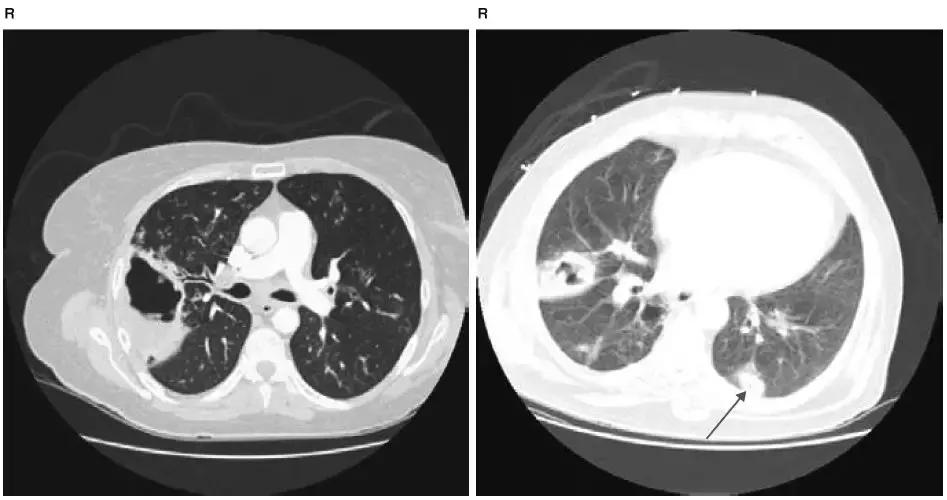

肺容积缩小

图4-3 CT显示左肺上叶肺不张:气管病变(CT难以发现)导致左肺上叶肺不张,上腔静脉(黑箭头)静脉造影剂显示部分充盈缺损

图4-4 CT显示左肺下叶慢性肺不张:充气减少出现肺容积的明显缩小,纵隔轻度左侧移位